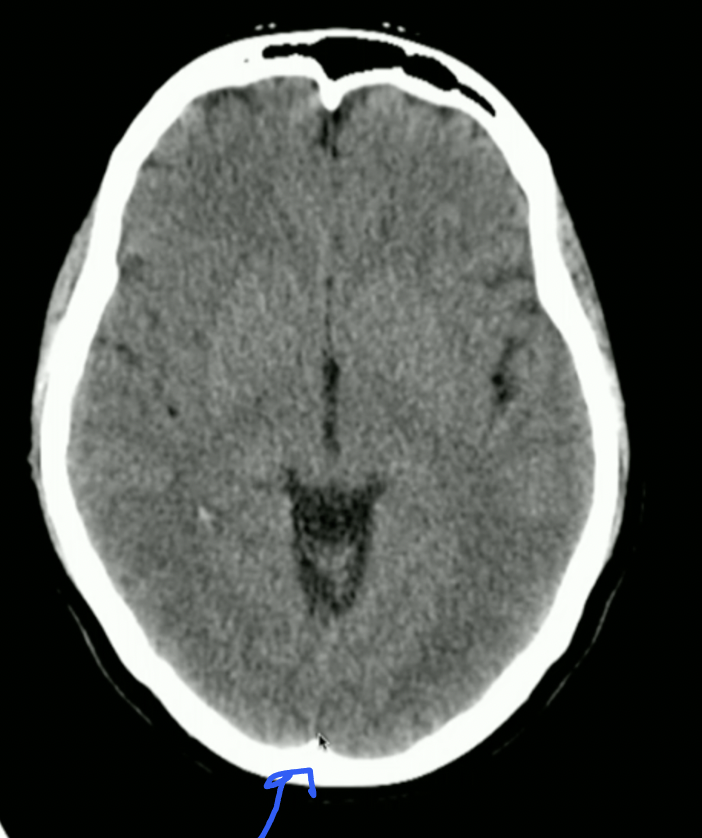

<p>What is the arrow pointing to? + Attachment Points</p>

What is the arrow pointing to? + Attachment Points

• Falx Cerebri

• Anteriorly: Crista Galli on Ethmoid Bone

• Posteriorly: Occipital Protuberance